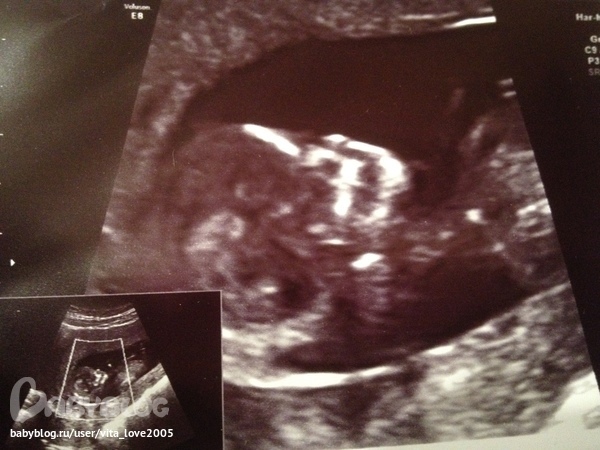

12 недель и 3 дня - 1 Скрининг. ручки по швам, ножки согнуты в коленках.))

а здесь только голова и шейка с плечиками чуть чуть, с 1 Скрининга. надо подалше оттойти чтоб понять.))